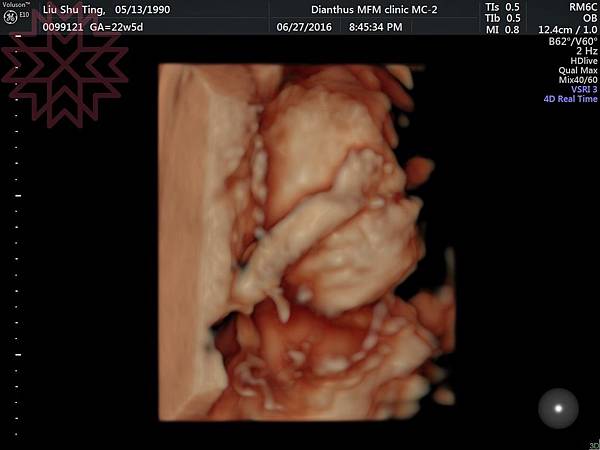

這是兩邊的小手~~

4D臉部照~剛好拍到葉黃素的裘莉式性感豐唇哈哈哈

超Q低~